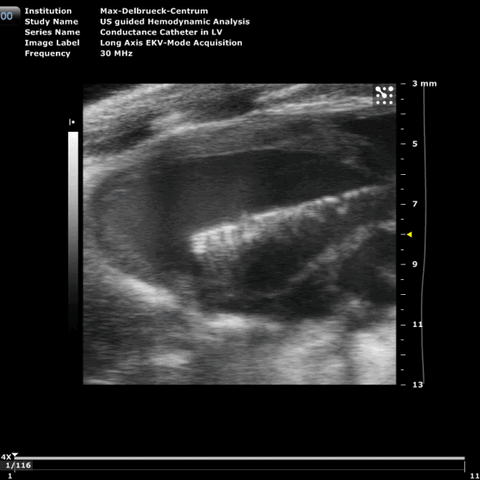

Echocardiografic image of a conductance catheter in the left ventricle of a mouse

Dank des technischen Fortschritts verfügen wir heute über Leitwert-Katheter, die klein genug sind, um in der präklinischen Forschung mit Kleintieren eingesetzt zu werden. Die Möglichkeit, Messungen intrakardial und in Echtzeit durchführen zu können, hat diese Technik zur führenden Methode bei der Bestimmung hämodynamischer Veränderungen in Tiermodellen werden lassen und die Untersuchungsmöglichkeiten in der präklinischen Forschung stark erweitert.